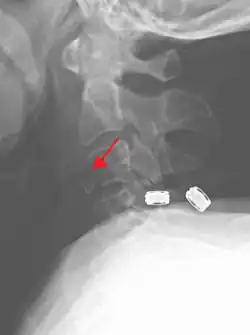

Radiographic detection

On CT scan or X-ray, a cervical fracture may be directly visualized. In addition, indirect signs of injury by the vertebral column are incongruities of the vertebral lines,[7] and/or increased thickness of the prevertebral space:[8]

![CT scan with upper limits of the thickness of the prevertebral space at different levels[8]](./CT_of_prevertebral_space.jpg)